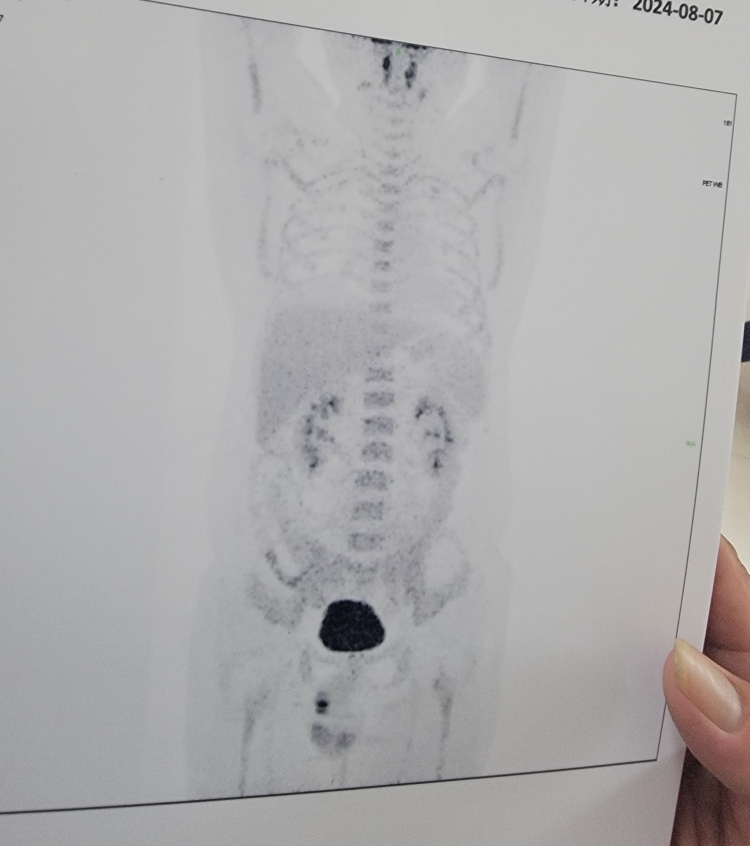

请问大家这是cr吗?

形态上好像没了,suv值是不是还有点高

这是第四疗结束后,第五疗之前的pet

只能说是pr

是不是那个suv值还有点高,得<2才行

其实理论上活性到3.5以下也算cr,没活性最好

还是有点高,医生怎么个意见

其实还是有效的,只是不够充分,听听你们主治的意见吧

还是太高了,没有活性最好